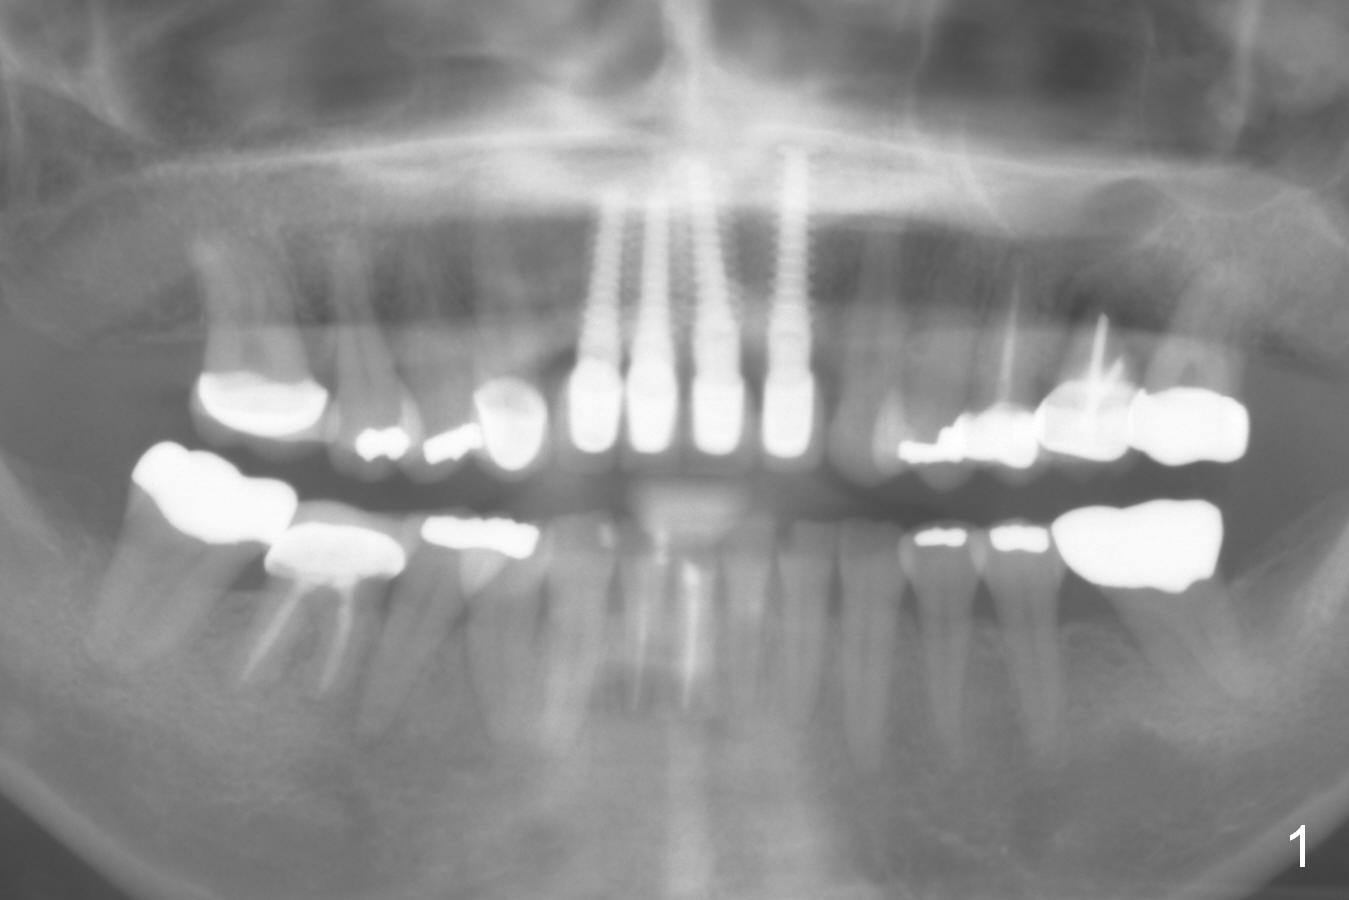

A 50-year-old woman has multiple restoration (Fig.1). She complains of upper left sensitivity. Exam shows that the tooth #14 has deep palatal pocket with purulent discharge. It appears that the palatal plate is lost (Fig.2 arrowhead). If it is confirmed after extraction (Clindamycin), an implant will be placed buccal to the center (septum). Collagen dressing or Osteotape (or preferably PRF if her veins are not too skinny) will be placed against the defective wall, followed by allograft. Use Magic Expanders or Sinus Lifter. Her bone is most likely not dense, since long implants are placed at #7-10.